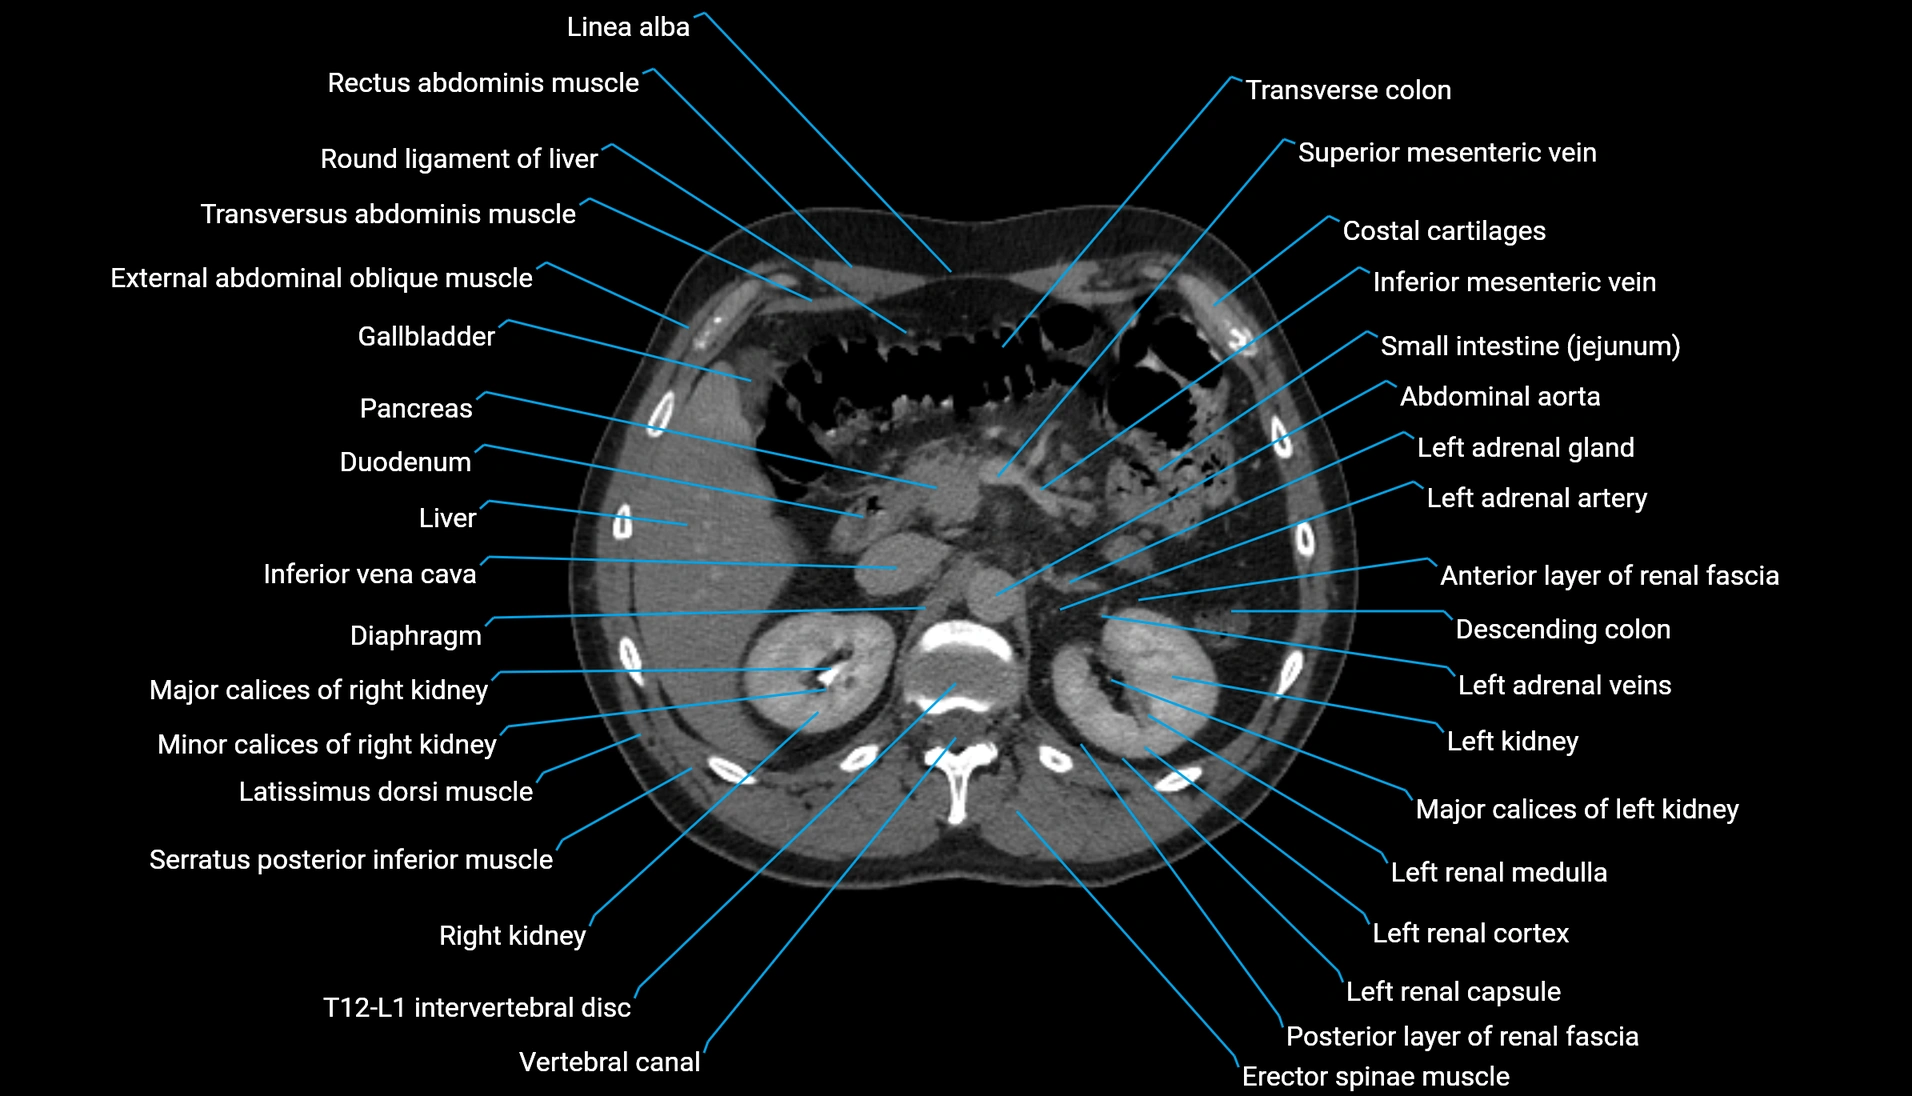

CT Appearance

Non-contrast CT:

-

Demonstrates cortical bone of acetabular rim in excellent detail

Detects fractures, dysplasia, retroversion, or bony overcoverage (pincer impingement)

3D reconstructions used in preoperative hip surgery planning

CT image